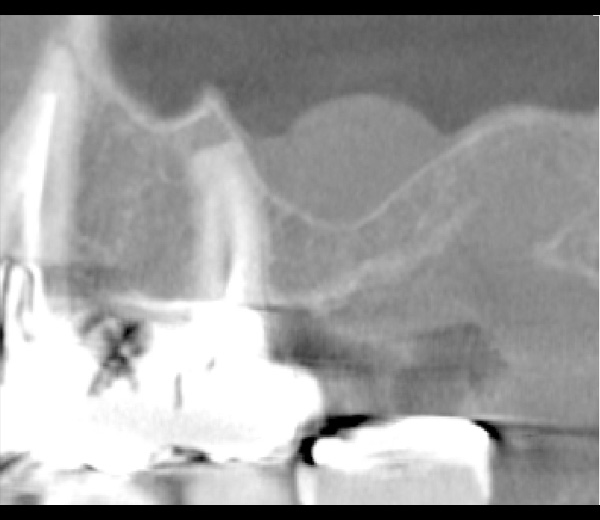

| 年代・性別 | 50代 女性 |

|---|---|

| 主訴 | 左上のブリッジがグラグラして外れそう |

| 治療期間 | 約18ヶ月 |

| 費用 | 1,600,000円 |

| 治療内容 | インプラント、骨造成、サイナスリフト、セラミック修復 |

| 治療に伴うリスク | インプラント周囲炎 セラミックの破折、脱離 |